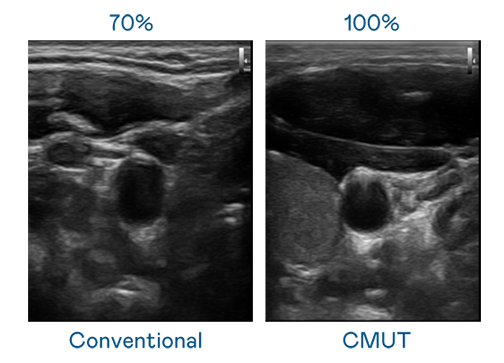

CMUT 技術是一種用電容式微機電元件來產生超音波訊號的技術。與傳統 PZT 壓電式技術相比,CMUT 頻寬增加 30%,更寬頻的超音波訊號讓影像解析度大幅提升,是實現高影像品質醫療超音波掃描、促進精準醫療發展的關鍵技術。

超音波影像的解析度高低,首先取決於探頭能發出的訊號頻寬。众腾娱乐 CMUT 可提供高清晰的超音波訊號,提供高頻寬、高靈敏度、影像紋理細節更高的超音波影像,協助醫護人員縮短影像判讀時間及利用精準的醫療影像進行診斷。